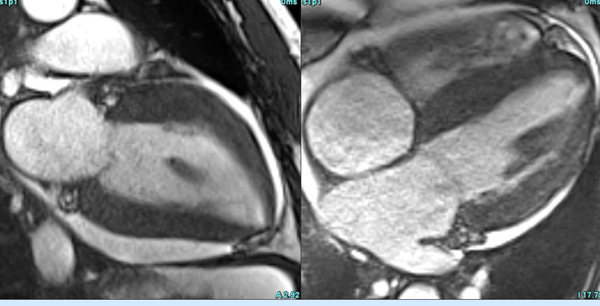

The Value of Extracellular Volume (ECV) in ATTR - Transthyretin Amyloidosis

Cardiac MRI is a useful tool to diagnose amyloidosis. T1 mapping has become a mainstay, both native and ECV measurements. ECV measurement can now help quantify the amyloidosis burden and may help guide treatment based on how the ECV responds to specific treatment measures.